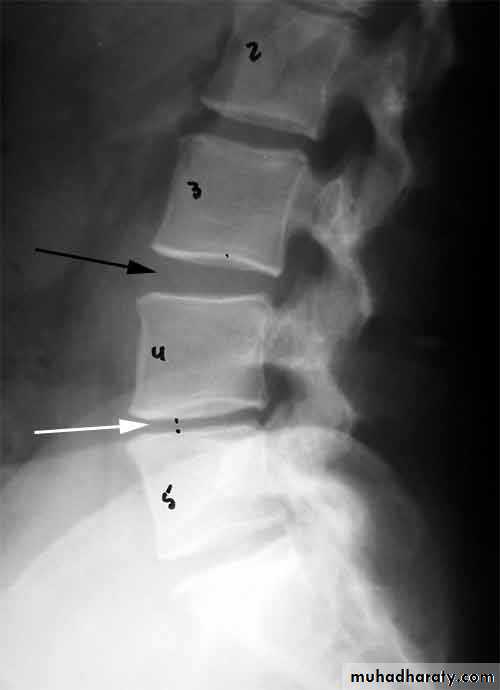

X-rays: show an abnormal narrowed disc space and to exclude bone diseases. After several attacks the disc space may be narrowed and small osteophytes appear.CT and MRI are more reliable than myelography.

Flattening of the disc space and marginal osteophyte formation appear later.• CHRONIC INTERVERTEBRAL DISC DEGENERATION

X-ray:Lateral views show the forward shift of the vertebra above on the vertebra below.

The gap in the pars interarticularis is best seen in the oblique views.